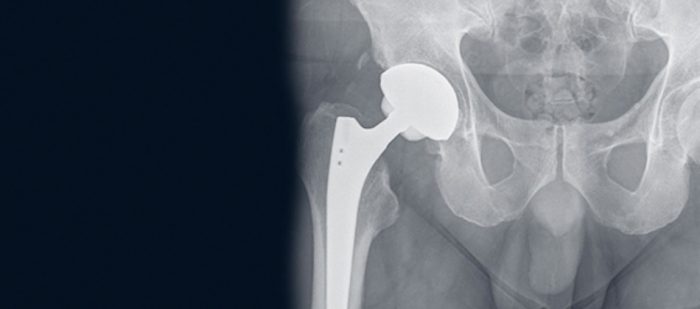

Ein künstliches Hüftgelenk kann bei einer fortgeschrittenen Hüftarthrose Beschwerden lindern. Was ist wichtig, wenn es trotz Prothese zu Problemen kommt?

Bei fortgeschrittener Hüftarthrose kann ein künstliches Hüftgelenk Schmerzen lindern und die Lebensqualität verbessern. Was erwartet einen vor und nach der OP? Auf einen Blick: Das steckt hinter dem Thema Eine Hüft-OP wird durchgeführt, um verschiedene medizinische Probleme zu behandeln und die Lebensqualität zu verbessern. Der jameda-Expertenratgeber beantwortet die neun häufigsten gestellten Fragen zu künstlichen Kniegelenken. Wenn körperliche Einschränkungen, Schmerzen sowie der Gebrauch von

Probleme mit künstlichen Gelenken – Ursachen und Therapie In Deutschland werden in jedem Jahr viele tausende Kunstgelenke implantiert. Nicht jeder Patient ist mit seinem neuen Immer mehr Menschen haben Probleme mit ihren Gelenken. Gelenkoperationen an der Hüfte und am Knie gehören zu den 20 häufigsten Eingriffen in Deutschland. Wenn alle